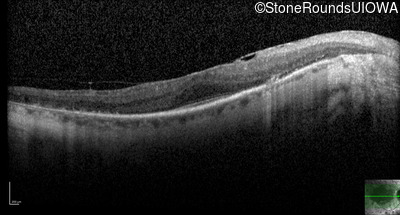

Optical Coherence Tomography - Left - 20/25 -2 sc

Exemplar / OCT Stack